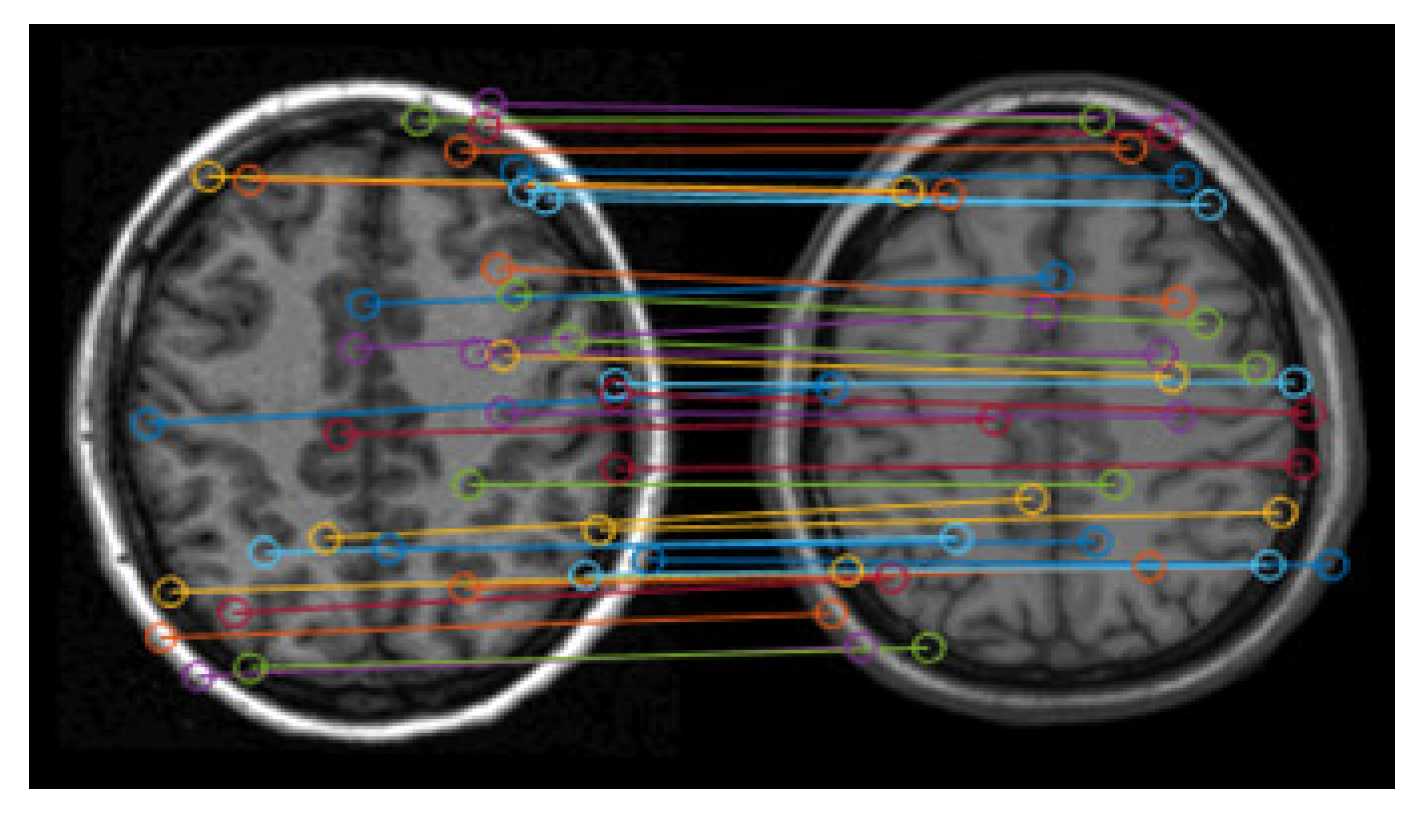

Figure 4 shows the matching results of the feature points. It can be seen that there are lots of error matching pairs of feature points, which may lead to the distortion of registration.

The accuracy of the matching pairs of feature points is the basis of correct registration. Therefore, the Random Sample Consensus algorithm (RANSAC) [21,22] is here used to eliminate the incorrect matching pairs based on the remaining feature points. Figure 5 shows the screening results based on Figure 4, which still includes relatively numerous feature points. The remaining points mainly exist at the brain tissue boundary, and their matching looks good for spatial location.

Figure 4. Matching results of feature points.

Figure 5. Remaining matching pairs of feature points.